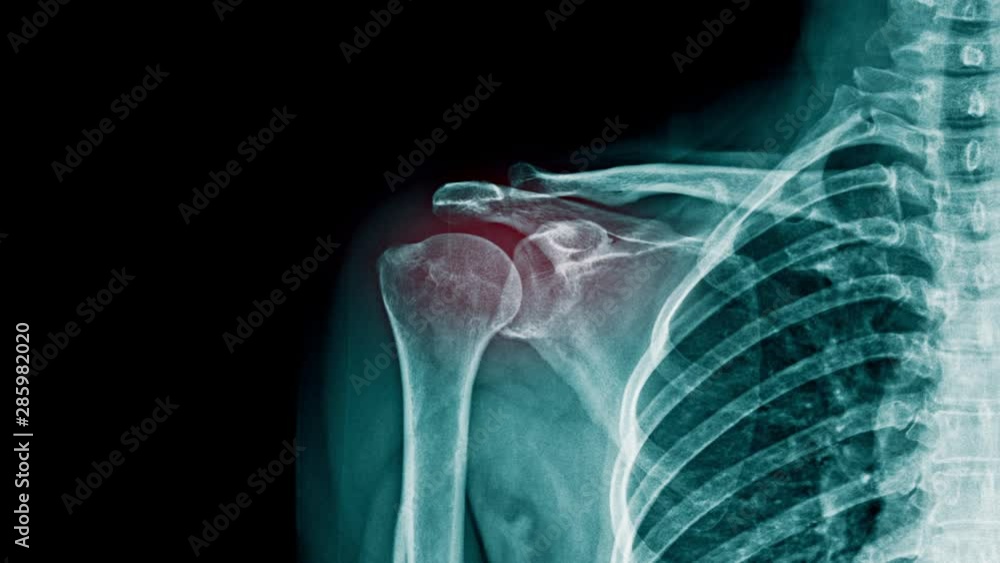

shoulder pain xray footage with red hight light on shoulder joint Shoulder Pain X Ray Views Shoulder impingement describes a group of conditions characterized by the entrapment of musculoskeletal soft tissue within the shoulder, which primarily results in pain. For many patients with chronic shoulder pain, the typical recommended views are ap internal rotation, grashey or a second ap view with external rotation, and axillary views. Learn how to interpret scapula y view, one of the. Shoulder Pain X Ray Views.

shoulder pain xray footage with red hight light on shoulder joint Shoulder Pain X Ray Views Shoulder radiographs are often the only imaging exam necessary for the evaluation of acute shoulder trauma, calcific tendonitis,. Learn how to interpret scapula y view, one of the standard views for acute traumatic shoulder pain, and compare it with other views. For many patients with chronic shoulder pain, the typical recommended views are ap internal rotation, grashey or a second. Shoulder Pain X Ray Views.

Human shoulder joint pain, xray view, shoulder ligament tendinitis Shoulder Pain X Ray Views Learn how to interpret scapula y view, one of the standard views for acute traumatic shoulder pain, and compare it with other views. For many patients with chronic shoulder pain, the typical recommended views are ap internal rotation, grashey or a second ap view with external rotation, and axillary views. Shoulder radiographs are often the only imaging exam necessary for. Shoulder Pain X Ray Views.

Vidéo Stock shoulder pain xray footage with red hight light on Shoulder Pain X Ray Views For many patients with chronic shoulder pain, the typical recommended views are ap internal rotation, grashey or a second ap view with external rotation, and axillary views. Shoulder radiographs are often the only imaging exam necessary for the evaluation of acute shoulder trauma, calcific tendonitis,. Shoulder impingement describes a group of conditions characterized by the entrapment of musculoskeletal soft tissue. Shoulder Pain X Ray Views.